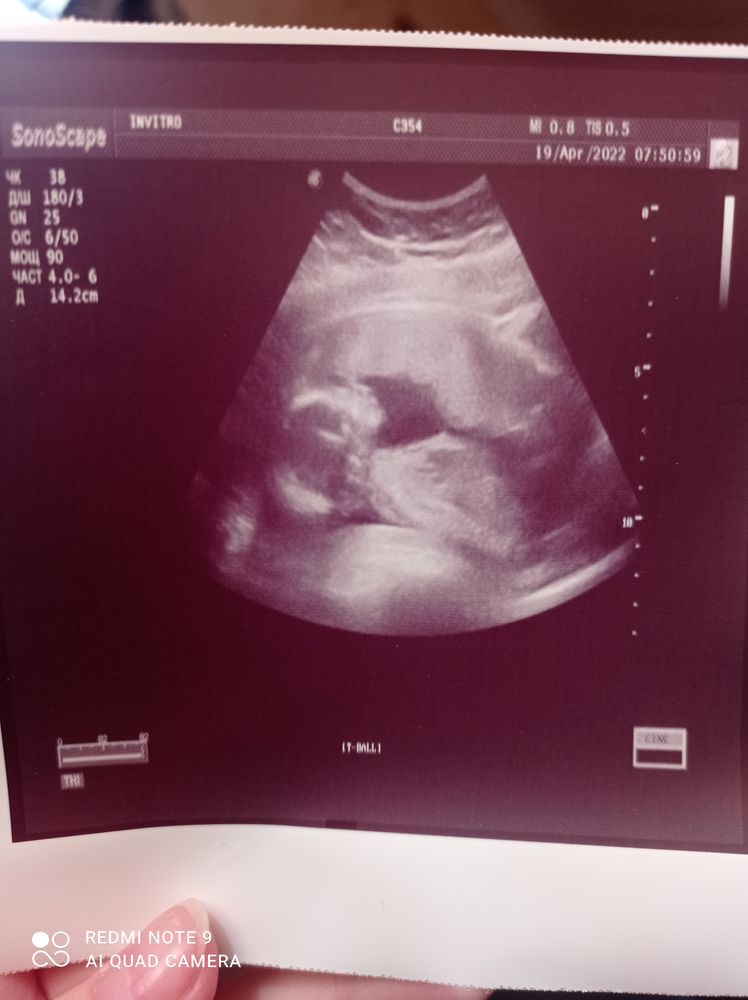

жду мальчика, 25 неделя Иваново

У нас будет СЫН💙💙💙